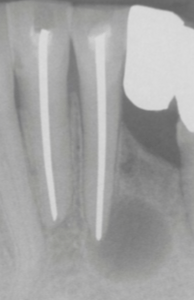

Cisto Periapical (radicular). Radiolucência bem circunscrita e extensa reabsorção radicular (fonte: Neville, 2016)